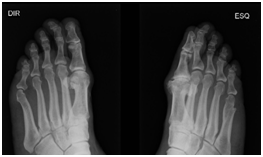

At the first day of treatment the patient was oriented to 30minutes sand walk at the beach once per week. According to Borg scale for pain in the second day the patient has grade 8 to the left inferior member (LIM) and 4 to the right inferior member. The Borg number falls to 5 in the third session to LIM. In the fifth session no pain was related by patient. It was use elastic therapeutic bandage (teraband) to sustain the foot under the metatarsus in both members. In the seventh day the patient managed to wear closed shoes without bother. In the re-evaluation with x-ray shows reduction of the bone protuberance on the Hallux (Figure 1 & 2).

Figure 2 X-ray of the feet showing a protuberance at the hallux in both feet that decreased, and the deformity is gone.

The application of elastic therapeutic bandage used in this study is known to have a correction effect on malalignment of the pelvis11 and shoulder,12 in addition to alleviating pain13,14 and grown of lymphatic circulation.15,16 Although there were differences with the present study in the method and duration of tape application, we reported that applying kinesiology tape after 23 sessions for this patient with moderate hallux valgus the HV angle effectively reduced as showed in the X-rays images. The walk at the beach sand and the treatment of ultrasound frequency and power with the aid of copper sulfate solution cooperate to the better results.